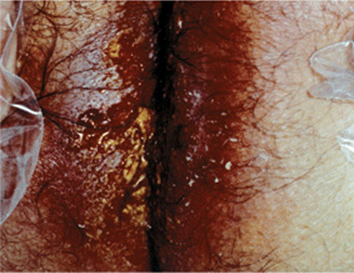

Cutaneous amebiasis begins as an indurated pustule that evolves to a painful ragged ulcer, foul smelling, and covered with pus or necrotic debris (Fig. 29-8). Usually a consequence of underlying amebic abscess invading skin. Typical sites are perianal area (extension of sigmorectal involvement) (Fig. 29-8) or abdominal wall (draining sinus from liver or colon). Penis or vulva may become infected during intercourse. Surgical wound infections may follow removal of hepatic or abdominal abscess. Remote ulcers (e.g., face) may result from autoinoculation.

Figure 29-8. Cutaneous amebiasis: perineum Perineal/perianal ulcer in a patient with rectal amebiasis.